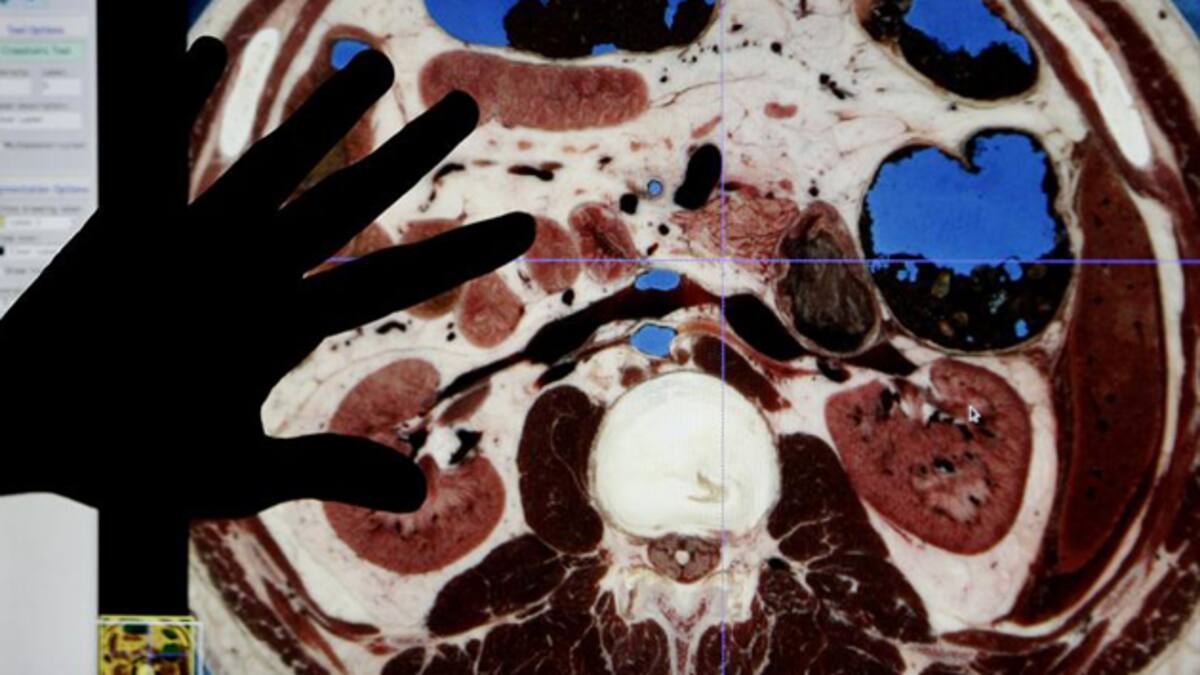

Bioteca Virtual 'es un atlas de la anatomía humana en 3D, completamente interactivo y realista', dijo a Colombia.inn, agencia operada por Efe, Jairo Castañeda, gerente de Numérica, firma que creó este software con el apoyo científico de la Universidad Industrial de Santander (UIS), de la ciudad de Bucaramanga (noreste).

Este programa, único en el mundo, permitió generar más de mil referencias a partir de imágenes reales de los sistemas, órganos y tejidos humanos, lo que lo diferencia de otras versiones creadas en Corea del Sur y EE.UU., según sus creadores.

Para diseñar el cuerpo humano, Numérica, empresa que comenzó hace 18 años a ofrecer servicios en el sector petrolero y en 2002 diversificó su oferta con un modelo tridimensional de la morfología de una rana dirigido al área educativa, se basó en 1.900 fotografías de secciones transversales del cadáver de un hombre realizadas por la Biblioteca Nacional de Medicina de Estados Unidos.

Esas fotos permitieron a sus ingenieros de sistemas y diseñadores recrear milimétricamente desde la médula hasta la piel, en imágenes disponibles en este atlas al que se puede acceder, previo pago de una licencia, desde un computador o un dispositivo móvil conectado a Internet.

Ballesteros también resaltó las ventajas de esta herramienta en el campo educativo, al señalar que se puede dar color a las imágenes de estructuras y órganos, aislar sistemas completos o visualizar diferentes detalles de una misma región mediante funciones por las cuales se agregan o retiran capas y secciones del modelo.